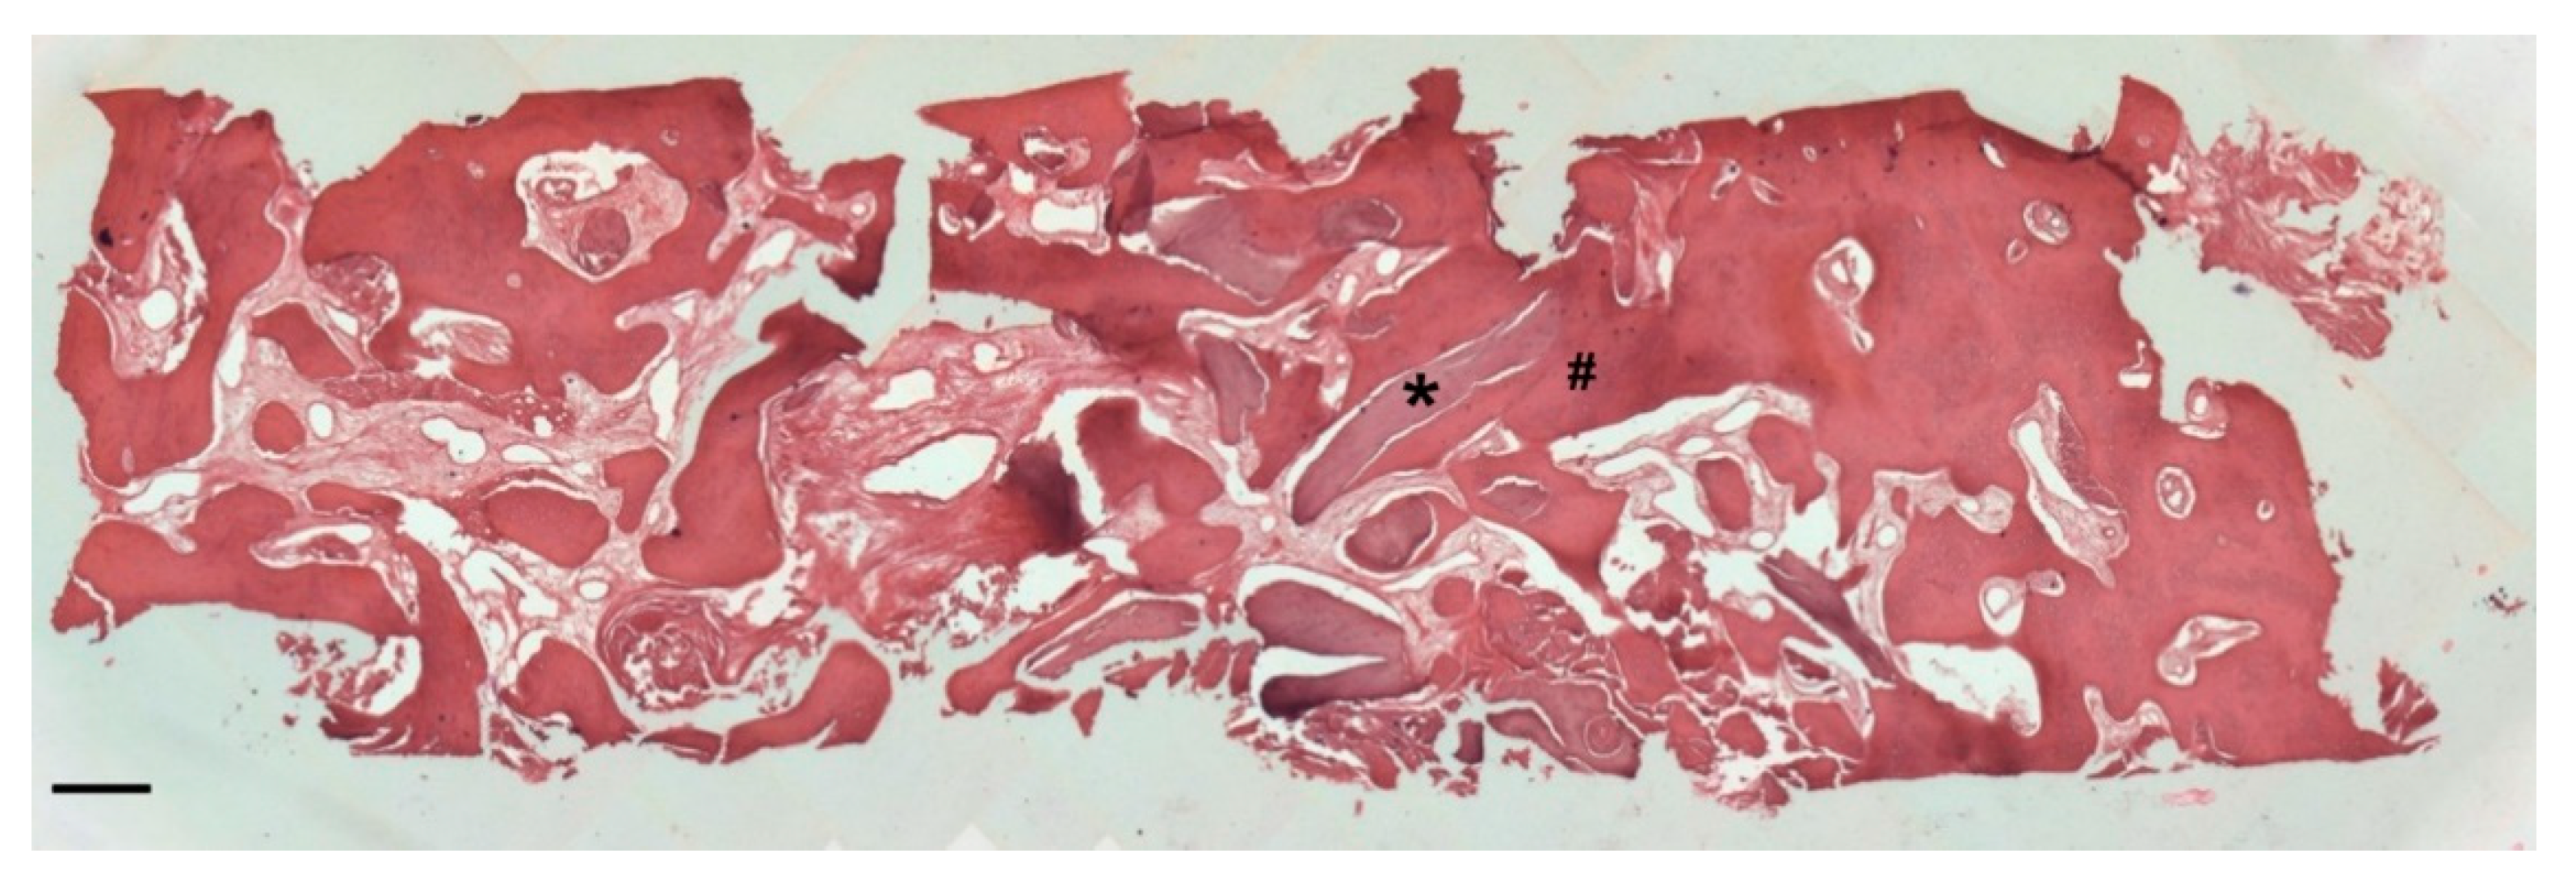

At low magnification, trabecular bone appeared to be surrounded by loose bone marrow. The large component of newly formed bone surrounded the few granules of biomaterial not yet reabsorbed (Figure 11).

Figure 11.

Two-dimensional (2D) reconstruction of the bone sample after staining with Hematoxylin and Eosin staining solution (magnification 25×, scale bar 400 μm). Bone trabeculae are dark-pink colored (#), whereas graft material appears light-pink colored (*).